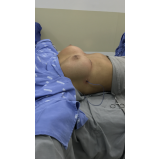

Mamoplastia de Elevação

Se você não sabe onde encontrar bons profissionais, equipe médica compromissada e sempre pronta a atender bem o seu cliente? Pois não se preocupe mais pois a FF Cirurgia Plástica coloca à disposição do cliente a possibilidade de contratar assistência médica pertinente que o possibilite submeter-se à mamoplastia de elevação.

Não pense duas vezes: conheça o consultório médico que realiza mamoplastia de elevação!

Praticidade pensada no que é mais adequado às necessidades do cliente, com profissionais de saúde por perto, levando maior segurança e eficiência até você. Busque com essa equipe todas as informações que precisa e saia satisfeito e tranquilo! Qualidade e bom atendimento você encontra de excelência na FF Cirurgia Plástica.